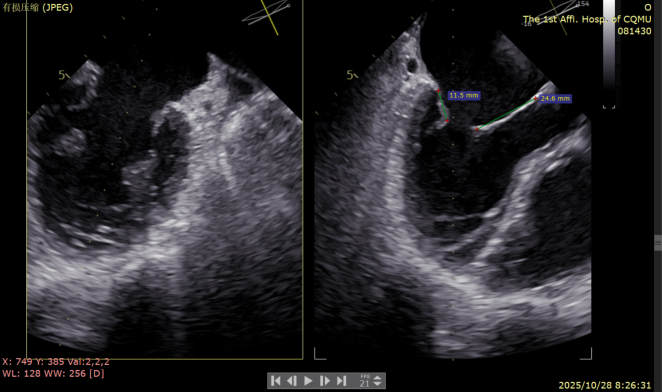

二尖瓣术前评估

复查TTE及TEE检查进一步评估二尖瓣情况。明确为FMR( Carpentier Ⅲb型),二尖瓣后叶栓系,2区瓣叶运动(视频2),重度FMR(4+), 肺静脉逆向血流;2区后叶长度1.15cm,2区前叶长度2.46cm,AP径3.2cm,瓣口面积5.1cm²,房间隔高度3.95cm,瓣叶无钙化,二尖瓣瓣膜条件适合行TEER手术。

图1、图2:2区瓣叶长度(前叶长度2.46cm,后叶长度1.15cm)及彩色血流

图3:房间隔可用高度>4cm